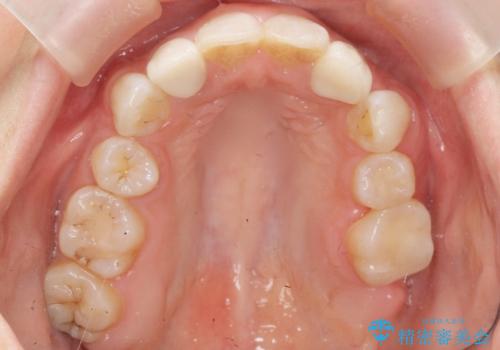

- 上の前歯の色と隙間を気にされ、来院された患者様です。

精査したところ、右上の側切歯(右上2)は神経が死んで変色しており、左上の側切歯と犬歯の間に2mm程度の隙間を認めました。

矯正せずに早く治したいという強いご希望により、セラミッククラウンによる補綴治療(上顎両側2の2本)を行いました。